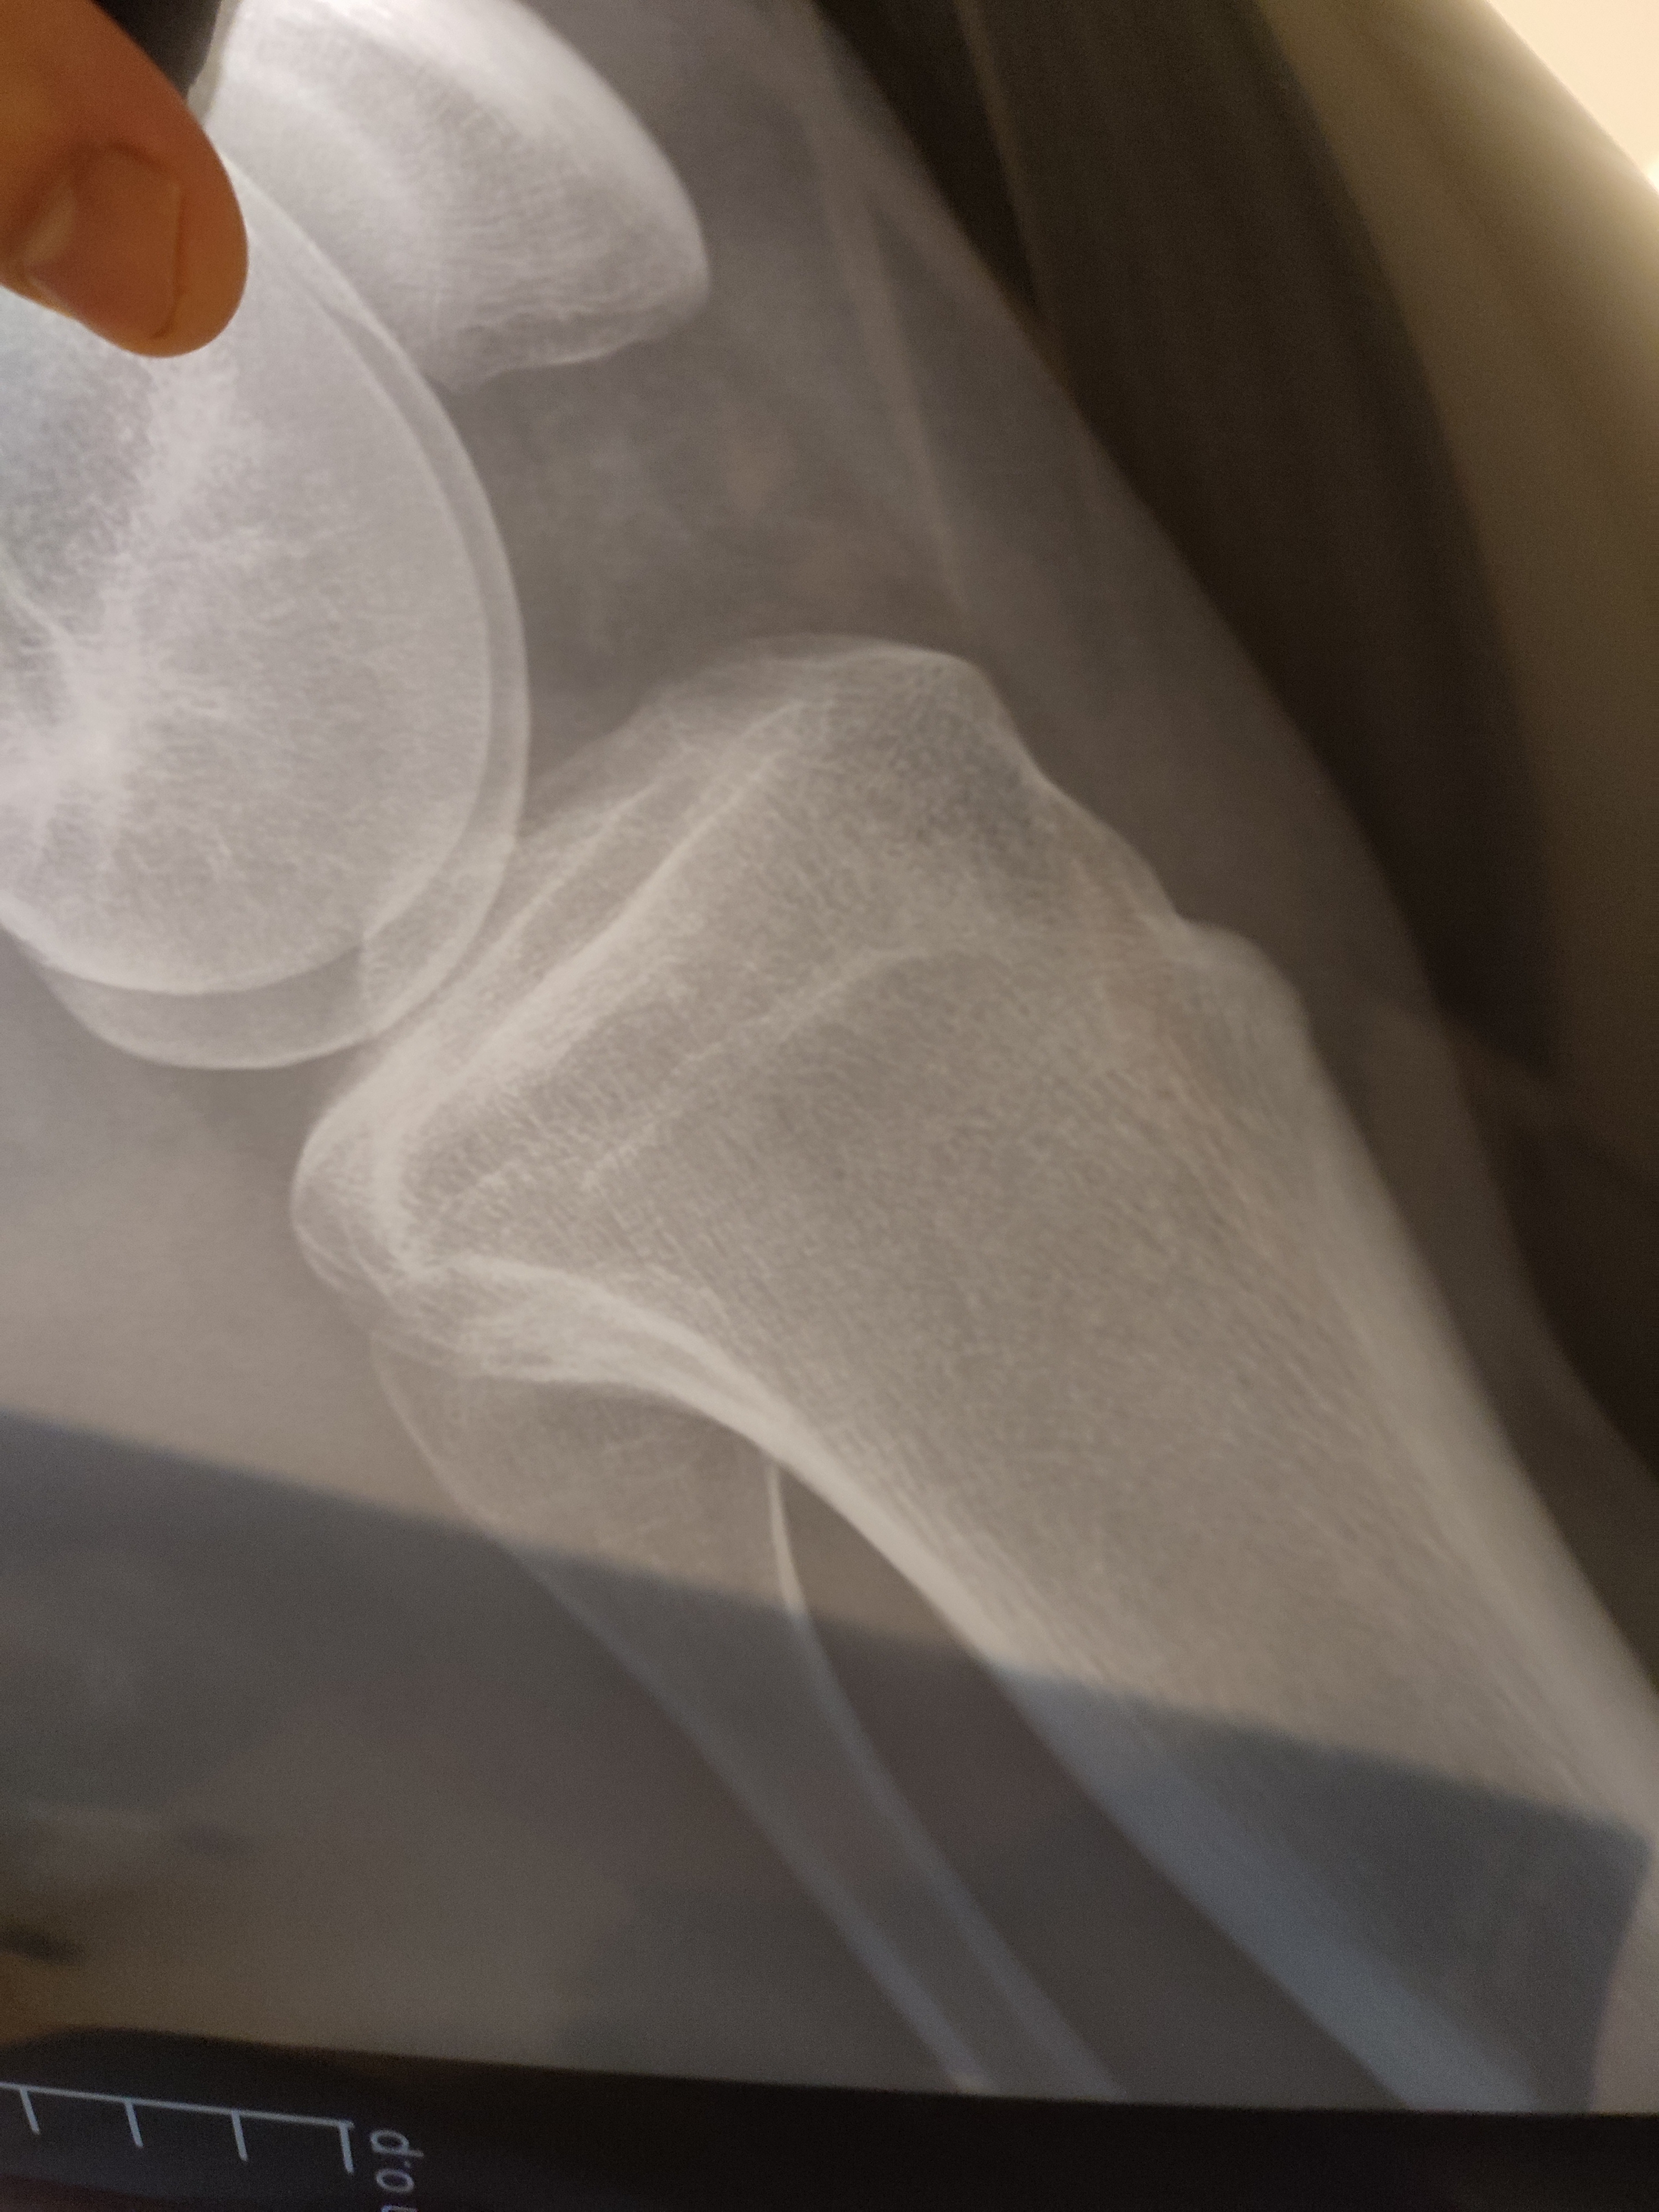

Здравствуйте, мне 22 года, мужчина, рост 182-183, отец 176, мать 164, можете предположить — есть ли ещё возможность вырасти в ногах? Если да, то насколько?

Заранее спасибо за ответ, фото снимков прилагаю)

На мой взгляд, закрыты

Андрей Юрьевич, в метаэпифизарной зоне бедренной кости просматривается линия просветления-её нельзя рассматривать  как зону роста?